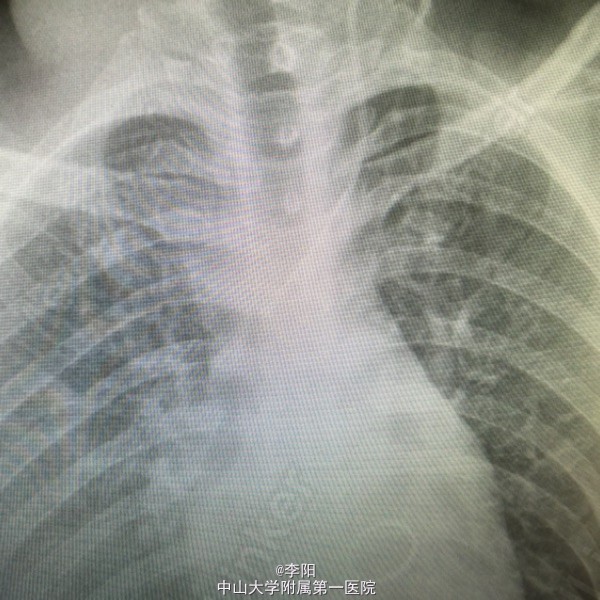

风湿性心脏病一例

风湿性心脏病

患者5年前出现劳动后乏力,气促,休息后好转,无胸痛,咳嗽,咳痰,无端坐呼吸,无颜面及下肢浮肿,当地医院就诊心脏彩超示:风湿性心脏病,我院彩超提示:风湿性心脏病,二尖瓣狭窄并关闭不全